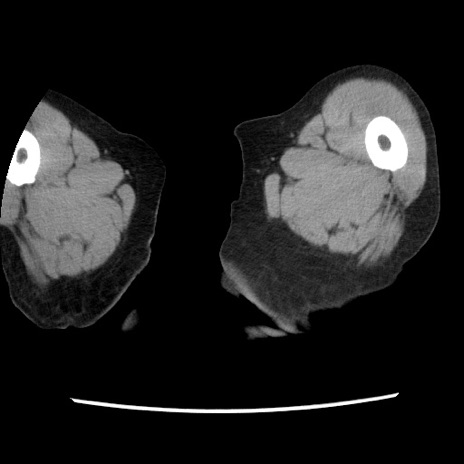

【症例】80歳代女性

【主訴】腹痛

【現病歴】8時間前から腹痛あり来院。

【既往歴】糖尿病、脂質異常症、子宮体癌にて子宮全摘術

【身体所見】意識清明・会話良好だが腹痛で苦悶様、全腹部にわたって反跳痛と圧痛あり

【データ】WBC 13600、CRP 0.14、LDH 224、CK 90